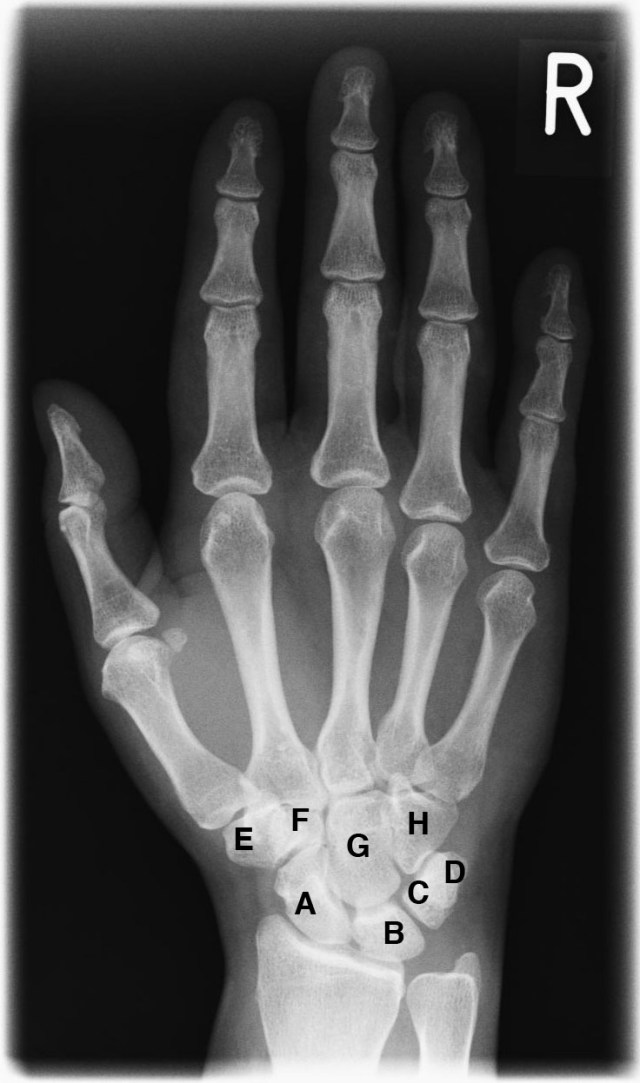

«Ein Schiffchen fährt im Mondenschein dreieckig um das Erbsenbein. Vieleckig groß, vieleckig klein, der Kopf muss bei dem Haken sein.»

A Kahnbein, B Mondbein, C Dreieckbein, D Erbsenbein, E großes Vieleckbein, F kleines Vieleckbein, G Kopfbein, H Hakenbein

La foto es de Wikipedia y ahí también se puede encontrar esa regla ligeramente modificada.